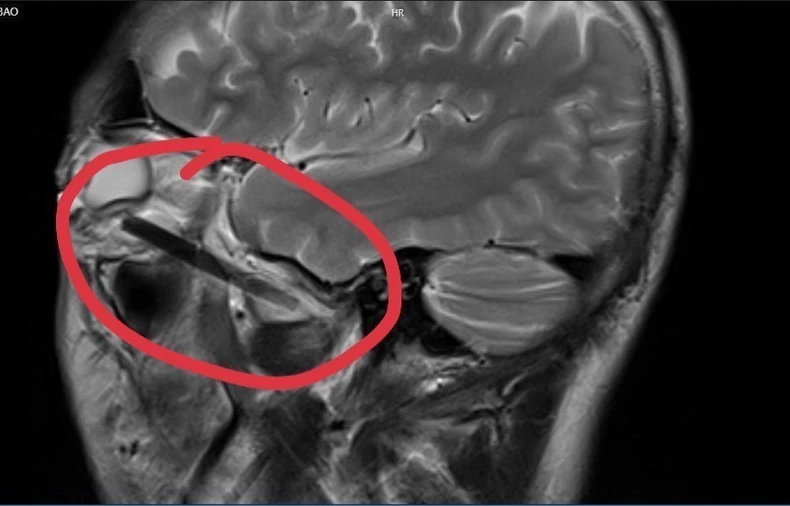

Các bác sỹ của Bệnh viện Đa khoa tỉnh Bình Dương đã phẫu thuật thành công lấy một phần chiếc đũa dài khoảng 6cm nằm sâu trong hốc mắt của người đàn ông.